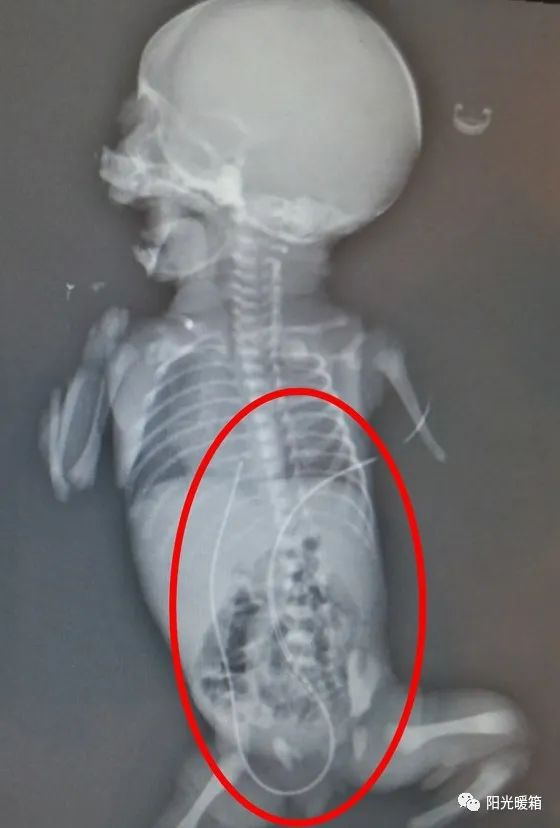

患儿出生后出现了呼吸急促、肤色紫绀、低血糖等表现,急需静脉通路输注抢救药物,且体重低下儿需长时间静脉营养支持,危在旦夕。在呼吸机辅助通气、温箱保暖等抢救措施稳定生命体征后,新生儿科团队立即给该患儿实施脐静脉置管术,过程顺利,导管内回血良好,术后X片提示导管位置正确。在出生后1小时内,救命的药物和营养液通过这根延续的“脐带”输送给了患儿,增加了抢救的成功率。目前,这根源源不断为患儿提供营养和抢救药物的脐静脉导管结束了它10天的使命,已顺利拔管。

医护人员为患儿成功插入脐静脉置管导管